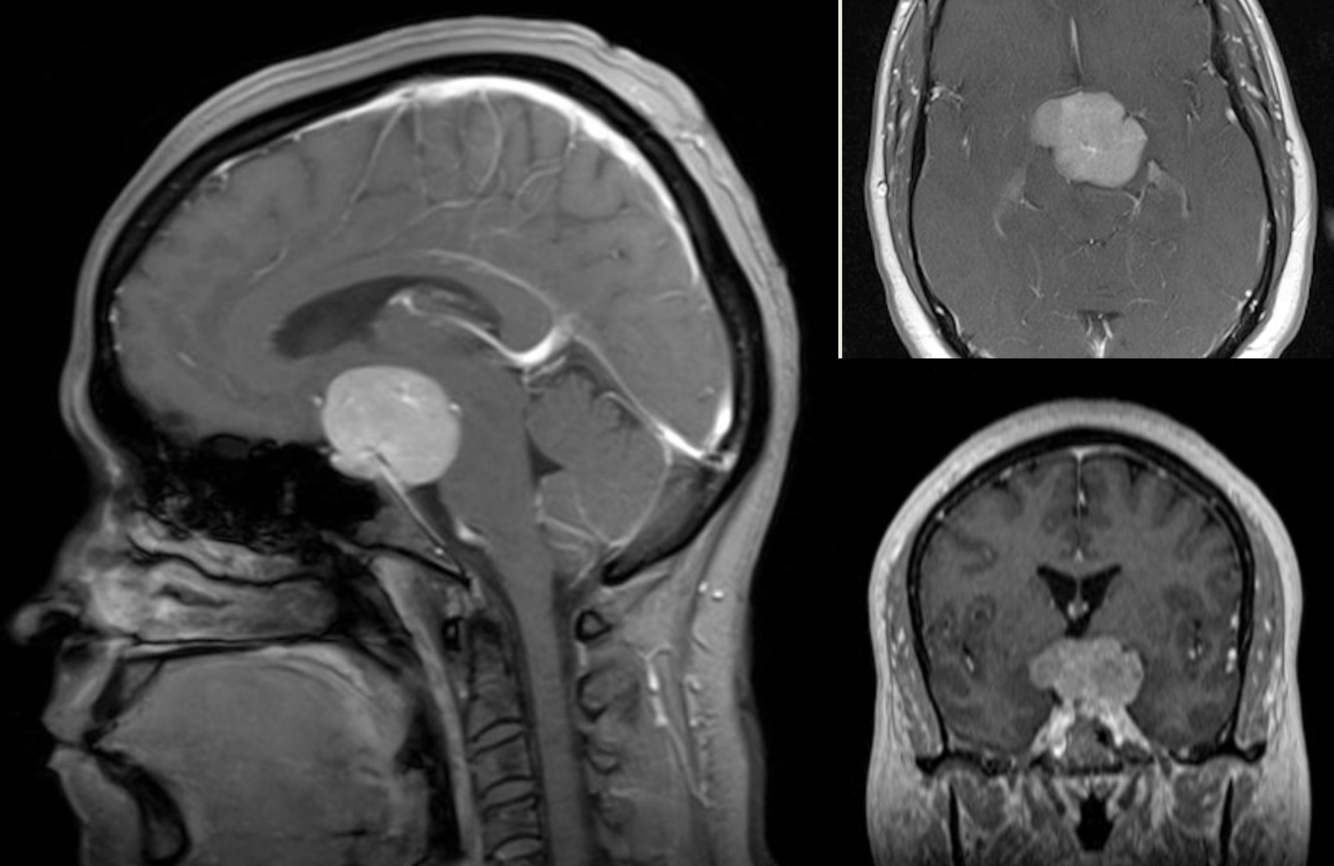

45 y/o M with bitemporal hemianopsia.

Meningioma arising from dorsum sella